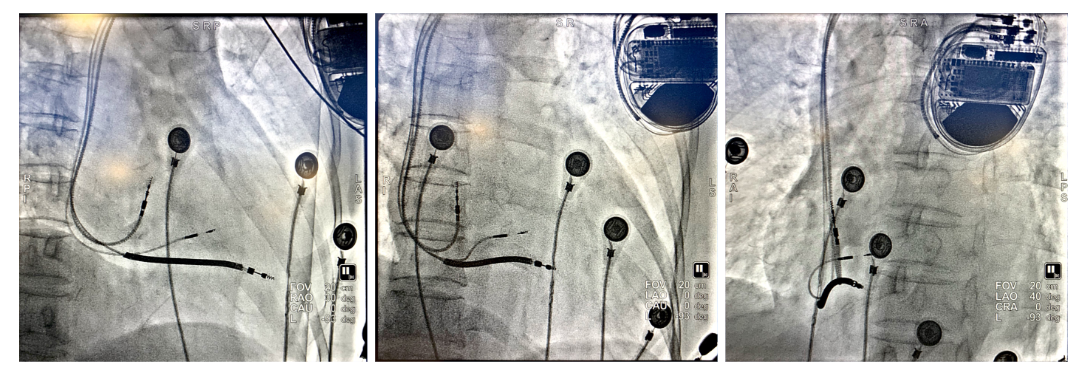

之后顺利植入心房导线及除颤导线,连接CRTD,调整AV间期融合右束支下传后得到完全正常化的QRS图形,起搏QRS时限97ms。

(上图从左到右分别为RAO 30°;AP;LAO 40°)